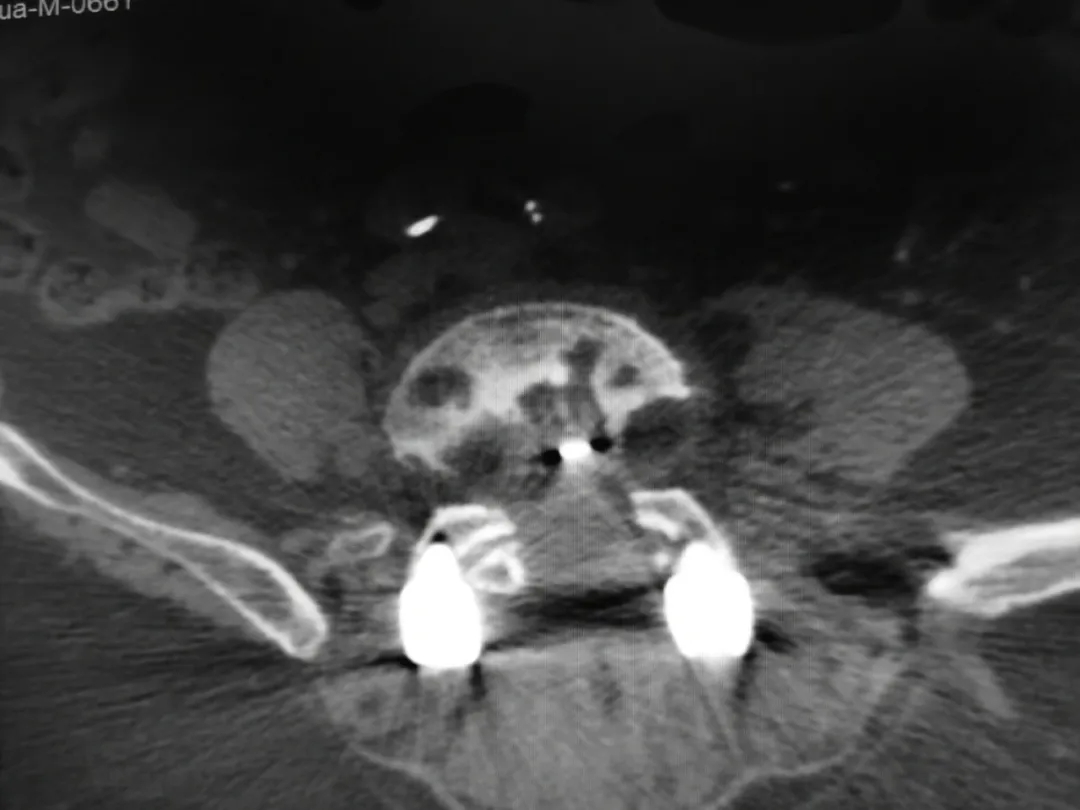

腰椎內固定術后影像:CT可見椎體多個低密度灶。

▲CT